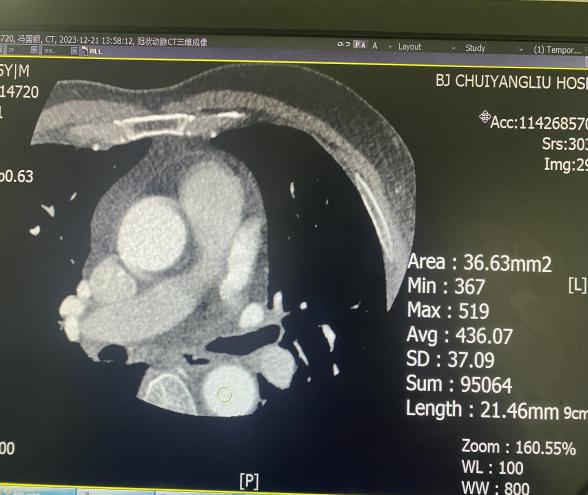

370mg/ml 60ml造影剂流速4.0ml/s和320mg/ml 60ml造影剂流速提高到4.6ml/s时CT值对比

我们可以看出,320mg/ml的造影剂流速提高的4.6ml/s时CT值和370mg/ml流速4.0ml/s时CT值接近,这就意味着单位时间内碘含量增加有利于血管强化,浓度较低的造影剂,通过增加流速血管强密度增高

320mg/ml÷1000×4ml/s=1.28 g/s

370mg/ml÷1000×4ml/s=1.48 g/s